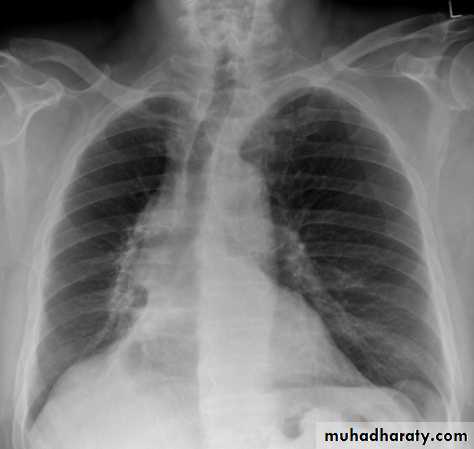

Right upper lobe collapse has distinctive features, and is usually easily identified on frontal chest radiographs .

Collapse of the right upper lobe is usually relatively easy to identify on frontal radiographs. Features consist of :

increased density in the upper medial aspect of the right hemithorax

elevation of the horizontal fissure

loss of the normal right medial cardiomediastinal contour

elevation of the right hilum

hyperinflation of the right middle and lower lobe result in increased translucency of the mid and lower parts of the right lung

right juxtaphrenic peak

A common cause of lobar collapse is a hilar mass. When a right hilar mass is combined with collapse of the right upper lobe, the result is an S shape to elevated horizontal fissure. This is known as Golden S sign .

Non-specific signs indicating right sided atelectasis are also usually present including:

elevation of the hemidiaphragm

crowding of the right sided ribs

shift of the mediastinum and trachea to the right